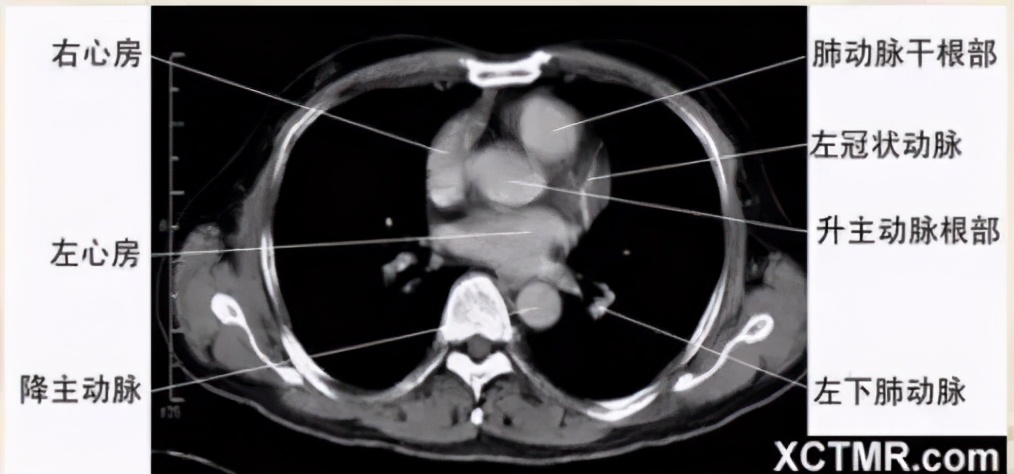

左心房层面